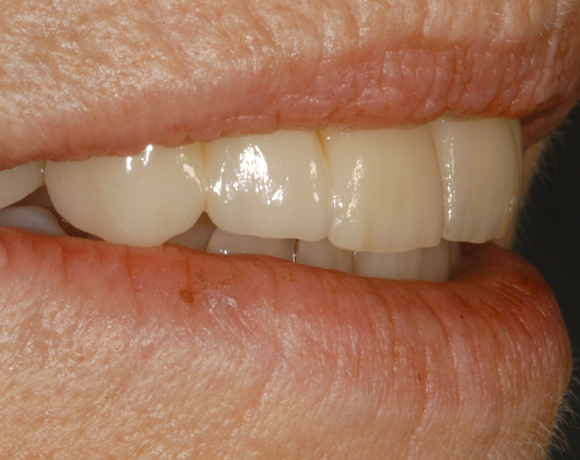

Bei dieser Patientin waren die Zähne 16, 12, 11 und 21 mit einer Modellgußprothese versorgt.

Als Ersatz wurden drei Implantate für die Zähne 13, 11, 21 gesetzt, die Lücke 15 – 17 mit einer

vollkeramischen Brücke versorgt. da die Patientin eine metallfreie Versorgung wünschte,

wurden Zeramex C Implantate gewählt, auch der Zahn 22 wurde mit einer vollkeramischen

Krone versorgt.